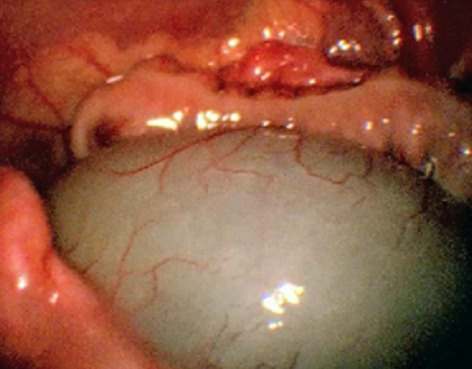

Result: The comparative analysis of the data shows a decrease in the number of presentations in ESU of AC cases during the pandemic, compared to the previous year, most often due to patients' fear of contacting the virus in the hospital environment. The median time between the onset of symptoms and the presentation in the ESU: 2020 – 14 days, 2019 – 5 days. Forms of moderate and severe AC predominated in the pandemic: GradeI—14.28%; GradeII—57.14%; GradeIII—28.57%. In 2019 GradeI—66.39%, GradeII—27.73%, GradeIII—5.88%. Laparoscopic cholecystectomy was attempted for all patients from the beginning, but the complications identified during surgery and severe forms led to a conversion rate in 2020 of 14.28%, compared to 5.88% in 2019. The severity of the cases is also observed in the postoperative complications encountered (perihepatic abscess Fig. 2. Figure 2, wound infection, bile leak; 2019—5.04%, 2020—23.21%), which required surgical reinterventions to solve them (2019: 2.52%, 2020: 10.71%). The number of deaths was significantly higher in 2020 (5.35%), compared to 2019 (0.84%).

Conclusion: Neglecting this pathology frequently encountered in ESU can lead to life-threatening complications and therefore we argue that a laparoscopically resolved cholecystectomy even in the "Covid19 era" remains the gold standard, guaranteeing the best results. Initially attempted conservative treatment may be a solution, but in the long term it can lead to severe complications and high costs.